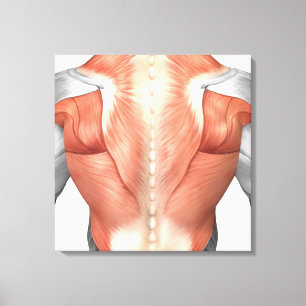

Impressão Em Tela Anatomia masculina do músculo da parte traseira 1

PreçoR$ 712,00

Produto oficialmente licenciado